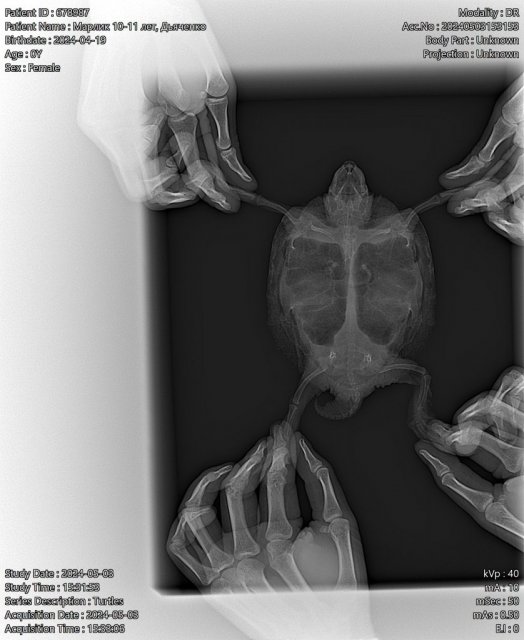

Вам нужно нести её на очный приём, чтобы как минимум сделали рентген и посмотрели почему её рвёт кормом, т.к. часто это симптом кишечной непроходимости. И онлайн диагностика тут просто ничем не поможет https://cherepahi.ru/servisy/catalog/spb-vet/

@moth Попали на приём к вету! Вроде бы, был именно черепаший специалист. Осмотрели, сделали рентген и укололи дексаметазон и байтрил. Пожалуйста, посмотрите назначения, норм? Меня удивила рекомендация ежедневных уколов Элиовита на протяжении двух недель.

@moth Я просмотрела часть врачей или всех, такие цены мне на данный момент не по карману, обратилась в клинику у дома. Во всяком случае, рентген же теперь есть, непроходимости на нём нет вроде?

@Светлана_34 Вы же понимаете, что сэкономив тут Вы в итоге потратите больше потому что заплатили в итоге за бесполезный приём, у Вас до сих пор нет диагноза, по одной этой проекции можно посмотреть лишь состояние жкт и более того, черепахе сделали не просто "неправильные" назначения, а конкретно вредные. Если бы Вы их выполняли всё как расписано - к концу курса был бы черепаший труп с отказавшей печенью и почками из-за дексаметазона и такой передозировки Элеовита. Это не тот случай, когда можно экономить

@Светлана_34 ей нужна как минимум ещё одна проекция для того, чтобы посмотреть лёгкие (номер 3 на картинке). Вы выполняли назначения которые Вам дали в клинике? на рентгене дата приёма 19 апреля, что из назначений Вы сделали?